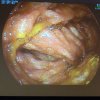

Képgaléria - UEGW 2014 Vienna